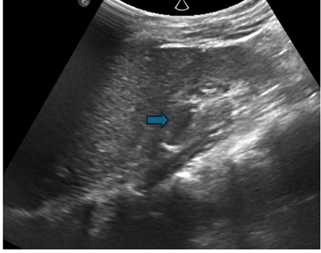

Figure 3: Ultrasound image of the right

kidney showing a triplex collecting system (

) with focal upper moiety

caliectasis. An increased parenchymal echogenicity and loss of

cortico-medullary differentiation